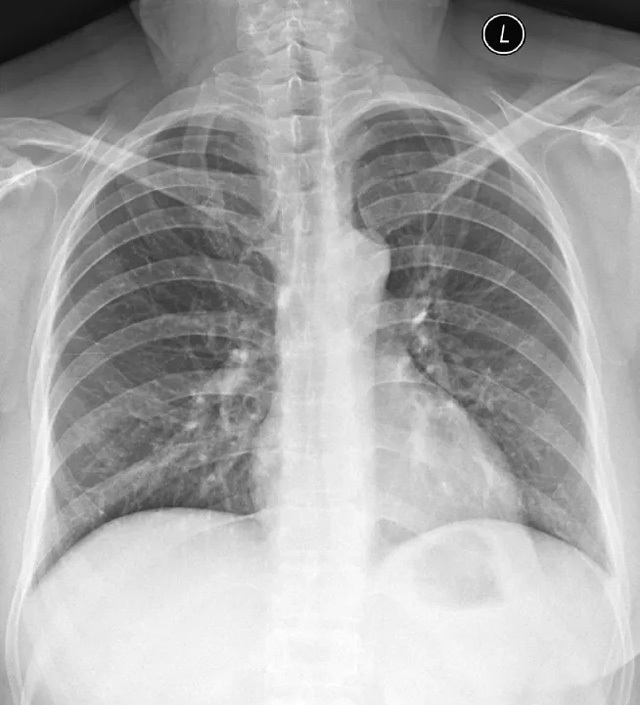

X線定位真空輔助旋切術是對臨床觸診和B超檢查均為陰性而X線片顯示的微小病變在X線立體定位引導下,將真空旋切刀置入乳腺可疑病灶區進行旋切及組織病理學檢查的一種乳腺微創新技術。

乳腺X線檢查發現可疑微小鈣化病灶成簇分布,BI-RADS:4類,且患側乳房臨床觸診和超聲檢查均為陰性。

部分BI-RADS 3類病灶,如果患者要求或臨床其他考慮,也可考慮活檢。

旋切范圍主要是評估鈣化灶的范圍而定,如果鈣化范圍較大,僅僅是作為取活檢的話,就旋切鈣化相對集中的位置就行。如果需要達到旋切治療的目的,那么僅僅是適合成簇的鈣化,即2平方厘米的范圍。

DR技術成像快、空間分辨率高,圖像清晰、細膩,是臨床不可或缺的常用基礎檢查技術。DR基礎成長營系列網絡課程,主要聚焦于臨床應用中大家關心的DR圖像質控、標準擺位及雙能成像技術,助力拍攝優質的DR圖像,提供更多影像診斷信息,服務于臨床診斷。